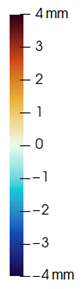

3.3. Simulation Error and Performance

4.1. Analysis of Simulation Accuracy

- Chin. Overall, the amount of error at the chin area is very low. This could be explained by the fact that the skin at the chin is very thin, and the coupling to the mandible makes the simulation highly predictive.

- Lips. In other regions, such as the lips, skin slides strongly over the underlying bones and teeth, and the deformation result is more difficult to predict. Overall, we observe higher variability in the error at the lips, and also some patients with higher error.

- Nose. The quality of the prediction of the deformation of the nose varies strongly across patients. In this case, the variability may depend on the type of surgery performed on each patient’s anterior nasal spine. This type of surgery is not easy to identify in the post-operative CBCT image due to the presence of bone grafts or fixation plates.

- Neck. Finally, we observe large error in the neck area (e.g., patients M5 and M8), and specifically at the junction point between the submental area and the neck (“C point” or “cervical point” in cephalometric analysis). This error was accounted for in our quantitative analysis, which negatively biased the overall results. However, this area is not of special interest to orthognathic surgeons. The deformation is known to be produced by a retraction of skin after surgery, but surgeons do not account for this effect during pre-operative planning.

- Segmentation of the maxilla and mandible. For all patients, the highest error (except for the neck, which is not clinically relevant as discussed above) appears near the cut areas, both of the maxilla (e.g., patients M5 and M7) and the mandible (e.g., patients M1 and M3). This is probably due to the presence of fixation plates and/or bone grafts in the real result (e.g., patient M10, whose maxilla was not segmented, but where the presence of bone graft has been confirmed by the surgeon who carried out the intervention). As a consequence, patients with a segmented maxilla and/or mandible show in general larger error than those without segmented bones. However, the smooth coupling method proposed in Section 2.3.3 reduces considerably the error in cut areas, as shown in Figure 2.

4.3. Comparison of Fine and Coarse Meshes